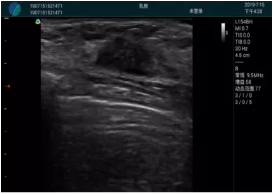

可視化甲狀腺穿刺引導(dǎo)

頸動(dòng)脈血流充盈飽滿,無外溢